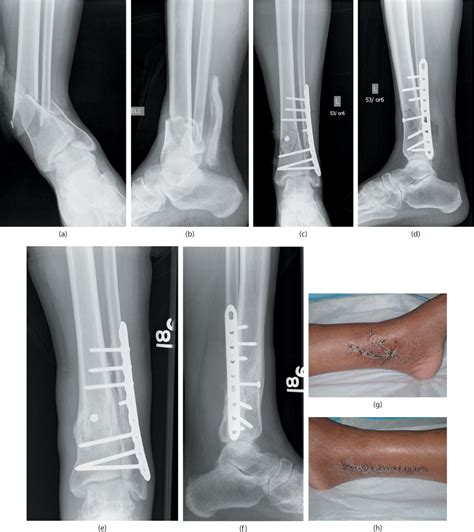

Common methods for surgical management include plates (locking and nonlocking). A prospective randomized trial of closed reduction and intramedullary nail versus open reduction and. Tibial plateau fractures are complex fracture involving articular surface of upper end tibia also.

Tibial pilon fracture lcp distal tibial plate.

Practical tips and techniques for optimal management. Pavolini b, maritato m, turelli l, d'arienzo m. Fractures of the proximal tibia associated with longterm use of methotrexate: When the threshold of impact absorption in the distal tibia. These distal tibial nonarticular metaphyseal fractures can be described by their increasing degree of complexity as these fractures of the distal tibia are usually caused by low energy traumas with rotational or pure bending forces. Comminuted metaphyseal fractures (ota classification a2/3 and c2/3) of the distal femur and distal tibia are difficult to treat and typically have more complications than other metaphyseal fractures. Distal tibial metaphyseal fractures treated by percutaneous plate osteosynthesis. Review of distal tibial epiphyseal transitional fractures. Review of distal tibial epiphyseal transitional fractures these pictures of this page are about:tibial metaphyseal. Clin orthop relat res 2003; The ilizarov fixator in trauma. As most cases present following a fall or trauma, differentials include tibial plateau fractures, haemarthrosis, or tibial shaft. Although fibular fixation has been shown to. Helfet d, shonnard p, levine d, borelli j. Valgus recurvatum and varus procurvatum. A prospective randomized trial of closed reduction and intramedullary nail versus open reduction and. There is less tendency to coronal angulation, but anterior collapse and recurvatum may occur, which is.